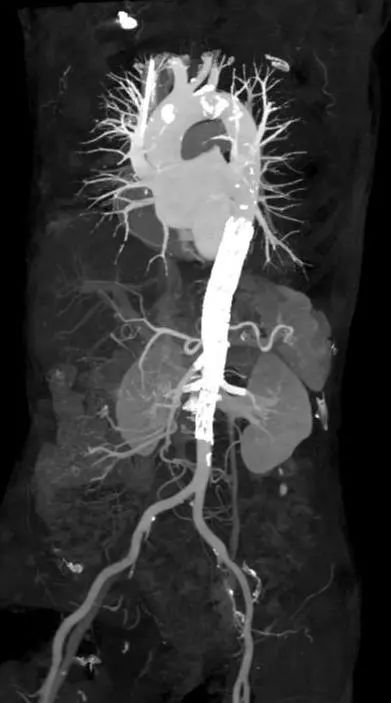

经过一系列精细的操作后,手术团队成功完成了腔内隔绝术,患者全身仅股动脉及肱动脉处有两处 1 cm 穿刺口。术后患者恢复良好,术后第七天 CT 复查提示「主动脉假性动脉瘤隔绝效果佳,内脏动脉支架通畅」(图 5)。

图 5